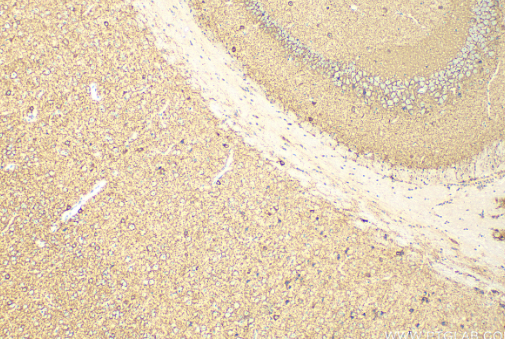

Immunohistochemical analysis of paraffin-embedded mouse brain tissue slide using (GAD67 antibody) at dilution of 1:400 (under 10x lens). Heat mediated antigen retrieval with Tris-EDTA buffer (pH 9.0)

Immunohistochemical analysis of paraffin-embedded mouse brain tissue slide using (GAD67 antibody) at dilution of 1:400 (under 40x lens). Heat mediated antigen retrieval with Tris-EDTA buffer (pH 9.0)